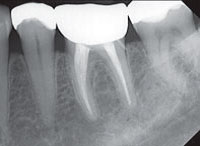

Цифровая  компьютерная   диагностика.

В нашей работе мы используем радиовизиограф HELIODENTPLUS – это интраоральная рентгенографическая система новейшего поколения немецкой фирмы «Sirona» дающая  высокое качество изображения при минимальной дозе облучения, что позволяет нам проконтролировать качество проведенного лечения.

Рентгеновские изображения, полученные на HELIODENT

PLUS, характеризуются высокой детализацией и контрастностью, что позволяет использовать их по широкому ряду показаний.